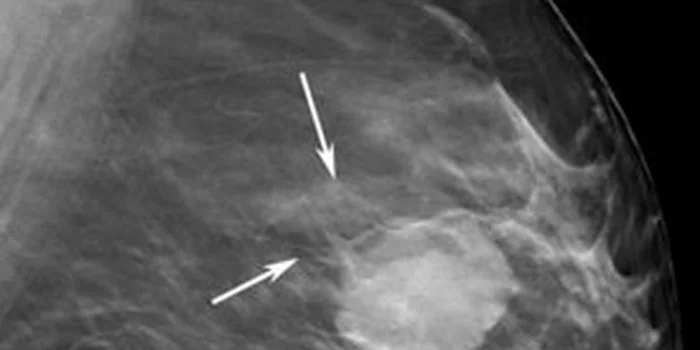

Dokter Spesialis Bedah Siloam Hospitals Balikpapan dr Esther Felicita Tambayong mengungkapkan, gejala kanker payudara yang mengarah keganasan dapat berupa benjolan dengan bentuknya tidak beraturan dan kebanyakan benjolannya tidak terasa nyeri.

“Biasanya diikuti dengan adanya perubahan dari warna kulit payudara pada penderita, bahkan jika sudah parah kondisi kulit seperti kulit jeruk yang disertai luka berbau pada bagian kulit payudara tersebut. Dan luka yang dialami terjadi tanpa sebab dan sulit untuk sembuh,” tutur dr Esther Felicita Tambayong, Sp B dalam keterangannya Sabtu (12/2/2022).

Melanjutkan edukasinya, dokter spesialis bedah ini menjelaskan beberapa gejala kanker payudara ditemukan juga terjadi dengan kondisi bagian puting yang tertarik kedalam dan bentuk payudara menjadi tidak simetris antara satu dengan yang lain.